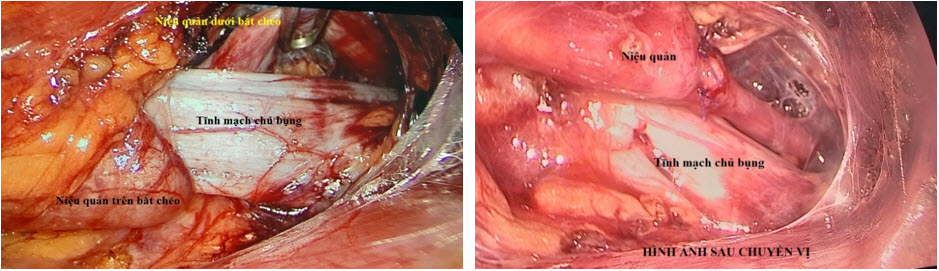

Bệnh nhân được điều trị bằng phẫu thuật nội soi sau phúc mạc

(retroperitoneal laparoscopy) với 3 trocar: cắt rời niệu quản tại vị trí bên phải

IVC, cắt bớt 1 đoạn niệu quản dư thừa, đưa niệu quản phải ra trước IVC, tái tạo sự lưu thông bằng nối niệu quản tận - tận có đặt ống thông JJ bên trong niệu quản làm nòng. Thời gian phẫu thuật là 60 phút. Diễn biến hậu phẫu thuận lợi, bệnh nhân được rút dẫn lưu ngày thứ 3 và xuất viện sau 5 ngày.

tietnieu4

Hình 4. Hình ảnh trước và sau chuyển vị

Trường hợp của chúng tôi được giải quyết bằng phẫu thuật nội soi sau phúc mạc. Do quen thuộc với các thao tác phẫu tích và khâu buộc sau phúc mạc nên cuộc mổ của chúng tôi thuận lợi không tốn thời gian. Thời gian 60 phút cho toàn bộ cuộc mổ là có thể chấp nhận được. Niệu quản không dính vào IVC nên phẫu tích tách biệt 2 thành phần này dễ dàng không phải để lại tại chỗ phần niệu quản nào. Chúng tôi cắt rời niệu quản bên phải IVC để có miệng nối rộng, dễ khâu. Tuy nhiên sau khi cắt rời và di động 2 đầu niệu quản, do niệu quản trên dài chúng tôi phải cắt bớt 1 đoạn niệu quản dư thừa  và tạo vạt thìa niệu quản phía dưới để khẩu kính 2 đoạn tượng đồng. Việc làm miệng nối và đặt JJ làm nòng khá thuận lợi, không cần phải đặt thêm Troca thứ 4.